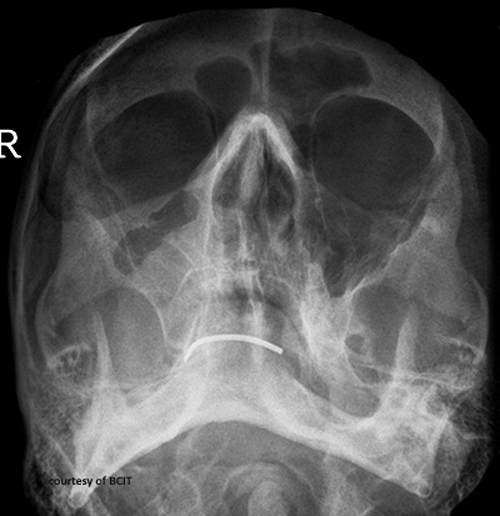

Which bones are most often fractured in facial trauma?

Mandible, maxilla, frontal bone, nasal bones, and zygoma.

Name the three LeFort fracture types.

Type I (horizontal), Type II (pyramidal), Type III (transverse).

What is the treatment for LeFort fractures?

Surgical stabilization with a multidisciplinary team.

Which sites are involved in a tripod fracture?

Zygomatic arch, orbital floor/rim, and zygomatic-frontal suture.